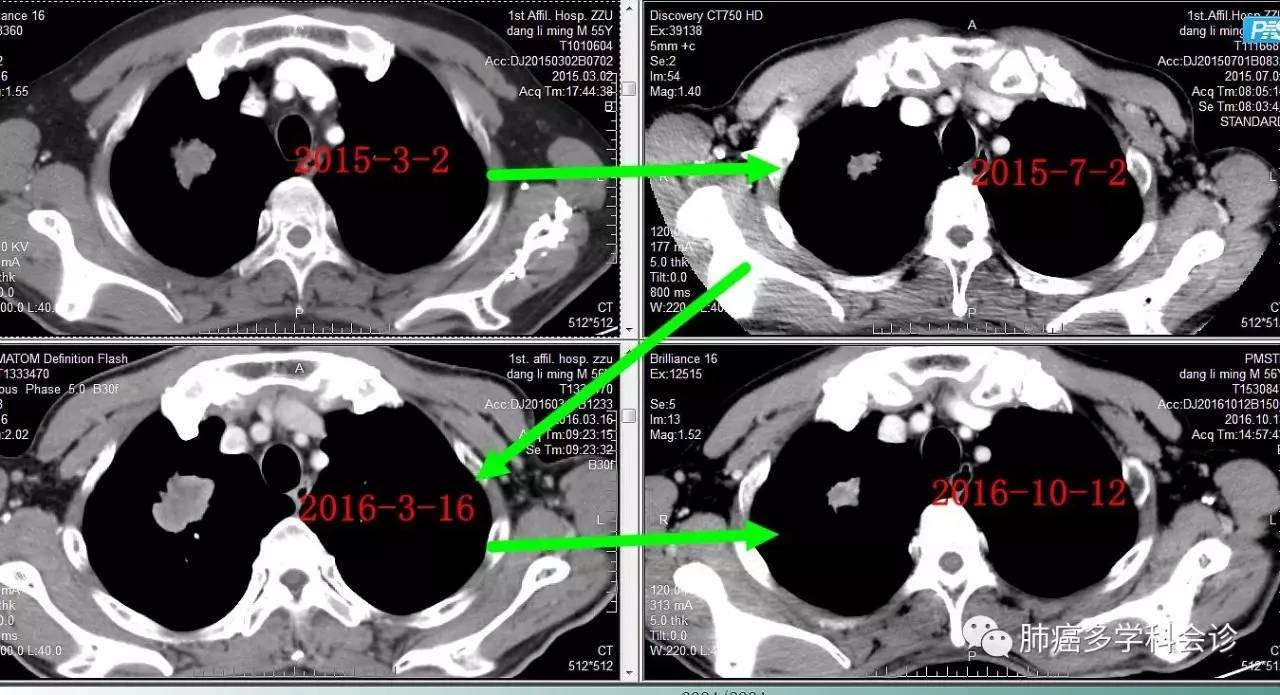

2016 年 3 月复查发现胸部肿瘤较前增大明显,确认为疾病进展,尝试奥希替尼,肿瘤再度缩小。

2016 年 10 月复查 CT 发现疾病又进展,给予“培美曲塞+卡铂”化疗 2 周期。患者因经济困难未能继续治疗。

微信图片_20170705104705.jpg微信图片_20170705104708.jpg下图显示了从诊断到吉非替尼治疗,进展后再用奥希替尼,肺原发灶和转移淋巴结大小的变化过程: